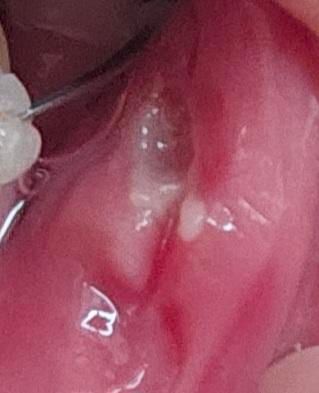

교정 중에 구내염 생겼는데 너무 아프고 교정기 때문에 더 심해지는 거 같아요

구내염 생긴지 2~3일 정도 됐는데

평소에 구내염 생겼을 때 보다 훨씬 아프고 밥도 못 먹겠어요

그리고 교정기 때문에 더 구내염 커지는 거 같고 상처 깊어지는 거 같아요..

• 1번 째 사진